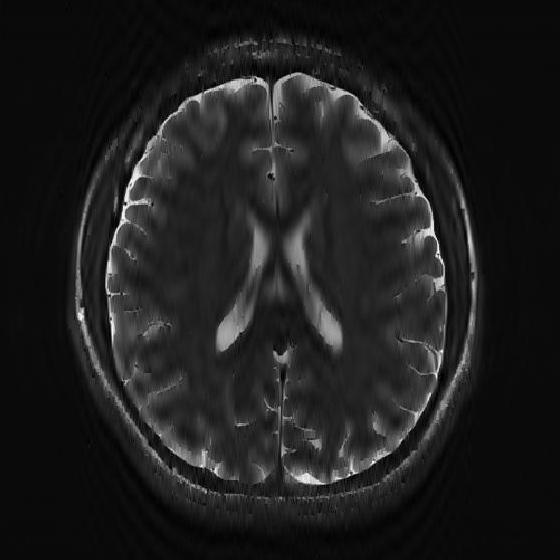

VII-D Application of the 2D-R-FFAST for MR imaging

In this section, we apply the 2D-R-FFAST algorithm to reconstruct a brain image acquired on an MR scanner with dimension . In MR imaging the measurements are acquired in the Fourier domain and the task is to reconstruct the spatial image from significantly less number of Fourier measurements [17]. To reconstruct the full brain image using 2D-R-FFAST, we perform the following two-step procedure:

Differential space signal acquisition: We perform a vertical finite difference operation on the image by multiplying the 2D-DFT signal with . This operation effectively creates an approximately sparse differential image, as shown in Fig. 11(e), in spatial domain and can be reconstructed using 2D-FFAST. Note, that the finite difference operation can be performed on the sub-sampled data and at no point we access all the input Fourier measurements. The differential brain image is then sub-sampled and reconstructed using a stage 2D-FFAST architecture. Also, since the brain image is approximately sparse, we take delay sub-streams in each of the stages of the 2D-FFAST architecture, instead of delay sub-streams as in the exactly sparse case. The 2D-R-FFAST algorithm reconstructs the differential brain image using of Fourier measurements.

-

•

Inversion using fully sampled center frequencies: After reconstructing the differential brain image, as shown in Fig. 11(f), we invert the finite difference operation by dividing the 2D-DFT measurements with . Since the inversion is not stable near the center of the Fourier domain, only the non-center frequencies are inverted. The center region of the 2D-DFT is fully sampled and used in the inversion process.

Overall we use a total of of Fourier measurements to reconstruct the brain image using the 2D-R-FFAST algorithm along with the fully sampled center frequencies. The resulting signal-to-noise ratio of the reconstructed image is dB. While the reconstruction error is not as good as state-of-the-art compressed sensing MRI results, we note that the 2D-R-FFAST has both low computational complexity and low sample complexity , which none of the state-of-the-art compressed sensing results in MRI can achieve.